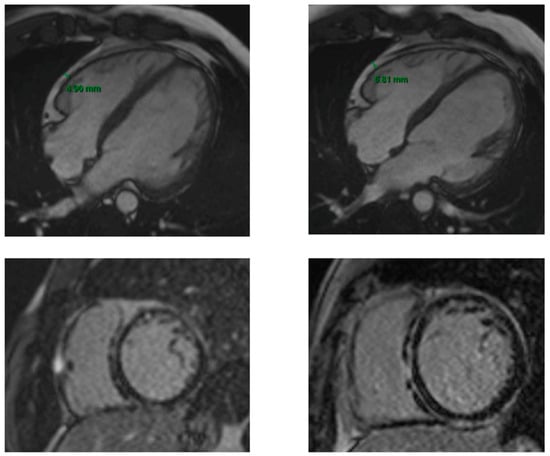

The EAT was slightly increased in the patients with ACM (16%) at the median timing of follow-up of 2 years and correlated with LGE extension and, consequently, severity of the disease (Figure 3).

Figure 3. First and 2-year follow-up CMR in a patient with ACM. The two upper images are SSFP 4 chamber sequences showing the EAT measure at the baseline CMR (on the left) and at the 2-year follow-up CMR (on the right). The two lower images are LGE sequences at the baseline CMR (on the left) and at the 2-year follow-up CMR (on the right). The increase in EAT at the 2-year follow-up corresponds to a greater severity of the disease, highlighted by a more extensive LGE (ring-like distribution on the LV and RV free wall involvement).